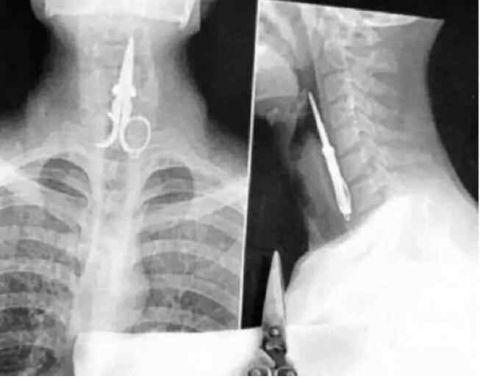

这个工人老说自己牙疼,检查后才发现这玩意儿